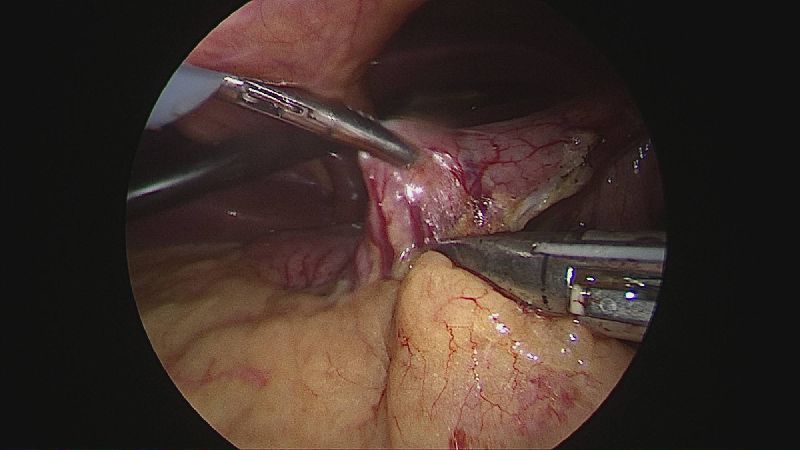

Operația ”de micșorare a stomacului” se realizează miniminvaziv (laparoscopic) și constă în îndepărtarea marii curburi gastrice cu păstrarea antrului gastric și a micii curburi sub forma unui tub calibrat pe o sondă.